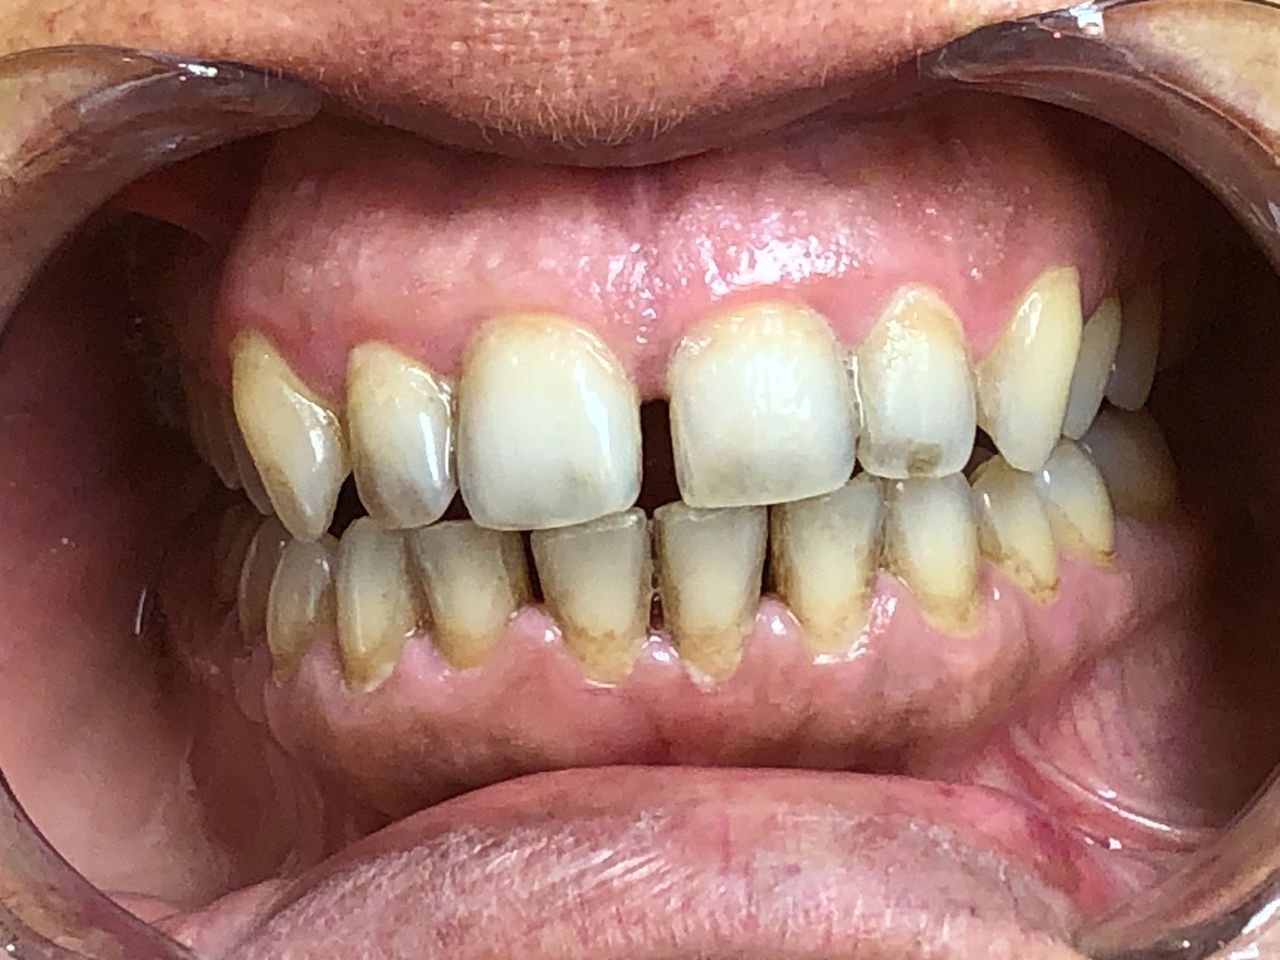

Foto e video

• M

Il Dottor Luca Strazioso ha qualità rare; mi ha ascoltata attentamente sin dal primo appuntamento, con la sua pazienza, competenza e professionalità durante ogni seduta ha ricostruito il mio sorriso, mi ha ridato la sicurezza che ormai avevo perduto. Posso affermare di essere rinata grazie alle sue mani, alla sua intelligenza e sensibilità. Inoltre, la Signora Antonella, assistente alla poltrona, è assolutamente insostituibile e generosa. Infinitamente grata ad entrambi.

• Studio Dentistico LUCA STRAZIOSO implantologia  •